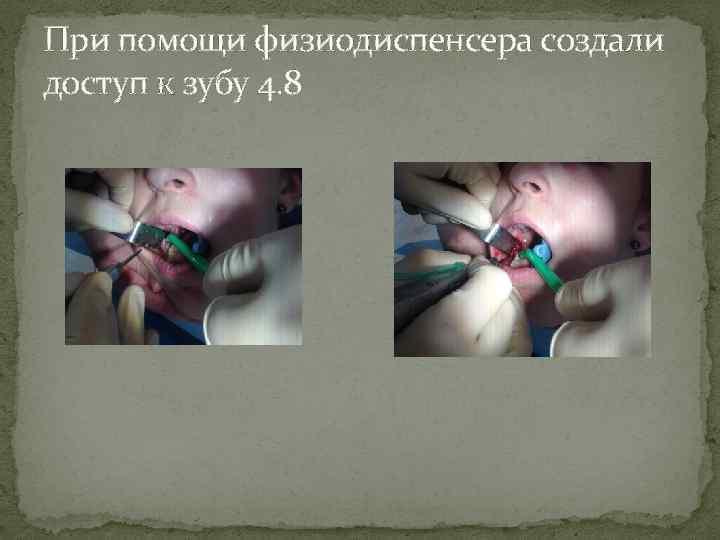

При помощи физиодиспенсера создали доступ к зубу 4. 8

При помощи физиодиспенсера создали доступ к зубу 4. 8